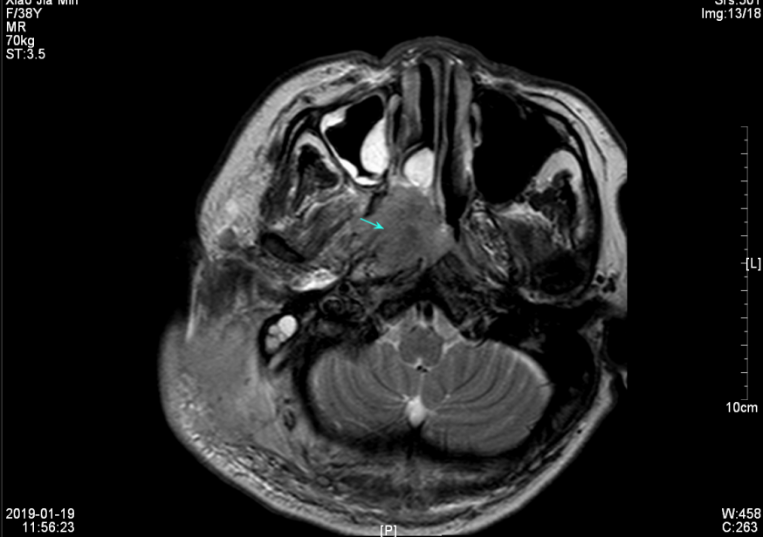

查颈部MR:1、鼻咽癌,并侵犯周围结构及颅底骨质,伴右侧颈部、咽旁淋巴结多发转移,与前片(2019年01月19日)比较,鼻咽肿块及转移淋巴结较前缩小(最大者约30mm×52mm)。2、副鼻窦炎,右侧中耳乳突炎(见图三、图四)。排除禁忌症,2019年3月9日、2019年3月30日行GX方案第3-4程化疗,方案:希罗达1500mg d1-d14+吉西他滨1.5gd1,8,化疗期间患者无明显不良反应。

▲图三 2019年3月11日 治疗两程后淋巴结MRI(30mm×52mm)

▲图四 2019年3月11日 治疗两程后鼻咽肿块MRI